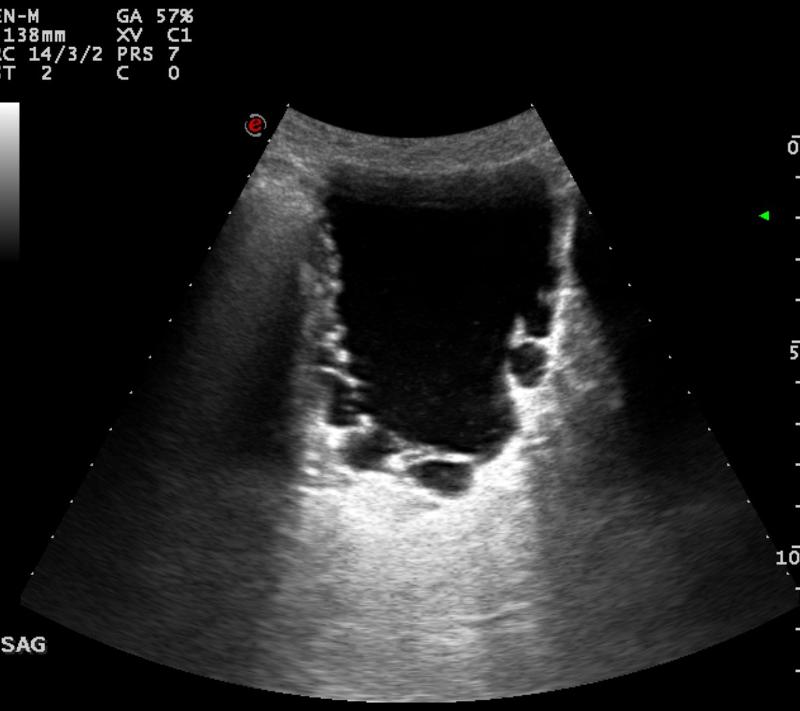

Male neonate

Posterior Urethral valves